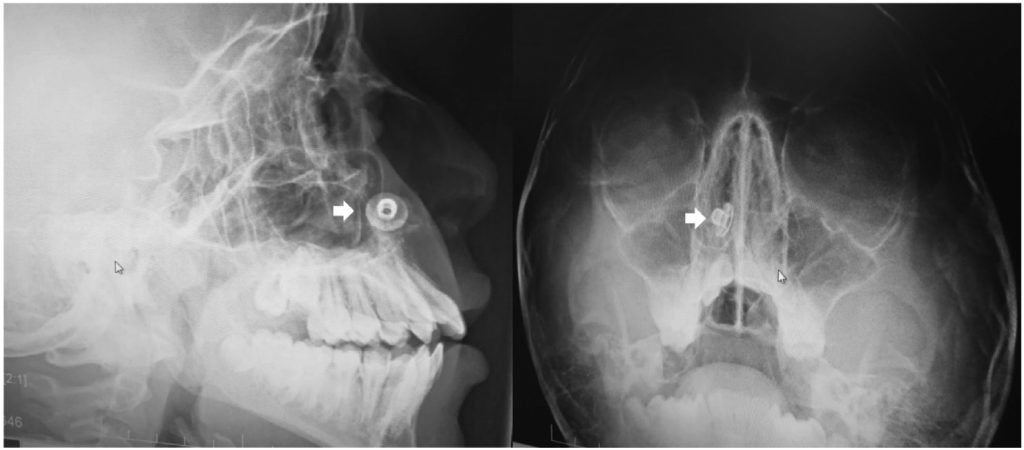

This rare case of symptomless foreign body obstruction became apparent during a routine dental radiography, Need To Know reports.

The teen, 17, denied ever having stuck anything up his nose and had no symptoms of anything being amiss – yet a small metal button was present in the floor of his nasal cavity.

Experts speculated that the button had likely been there for over a decade in a recently published medical journal.

“A CBCT confirmed the presence of the foreign body with associated mild inflammation, but no significant bony damage or sinus involvement was observed.